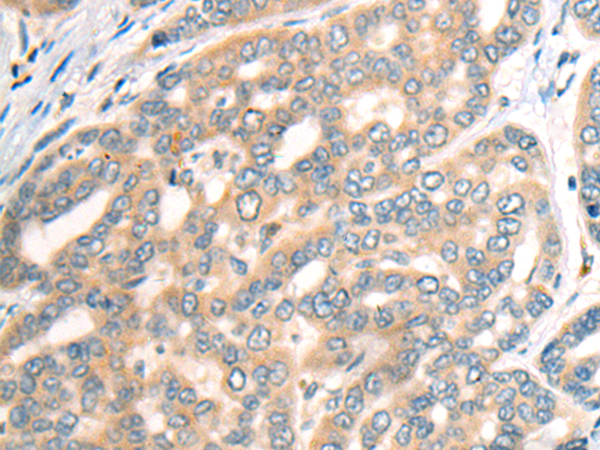

分类: 科研抗体货号: P09471别名:应用: IHC反应种属: Human, Mouse